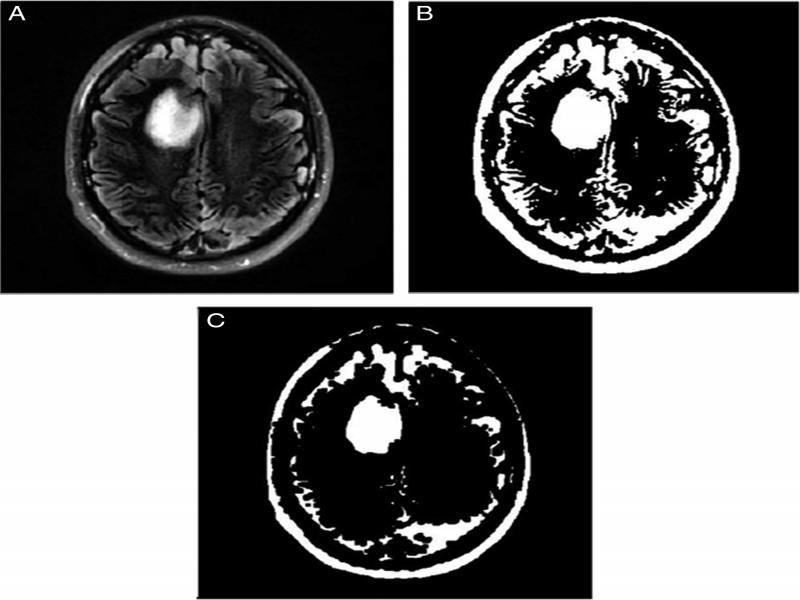

Thresholding: The threshold algorithm is now executed. In this, a threshold value based on the average of all intensity values is set. Pixel intensities more than the threshold value are set as one and the ones less than the threshold value are set as zero.

Watershed segmentation: The image obtained after threshold algorithm is complemented before being used for watershed segmentation. Complementing the image involves conversion of 0s in the threshold matrix to 1s and vice versa. In watershed segmentation, the entire image matrix is viewed as the watershed area where the image region is the catchment basin and the edges of image objects are the ridgelines. The brighter the pixel, the higher it is in the catchment region. The local maximas obtained using watershed segmentation are region based and the pixel intensities are grouped accordingly (Sara et al., 2019) (Figures 5 and 6).

Figure 5:

Processing (A) Thresholding, (B) Complement of image, (C) Image after watershed segmentation.

Figure 6:

Processing and post-processing techniques.